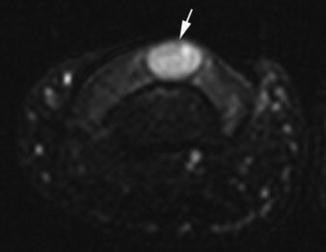

Glomus tumor of the nail bed. Axial T2-weighted MR image with fat suppression shows a 2 mm markedly hyperintense lesion of the nail bed